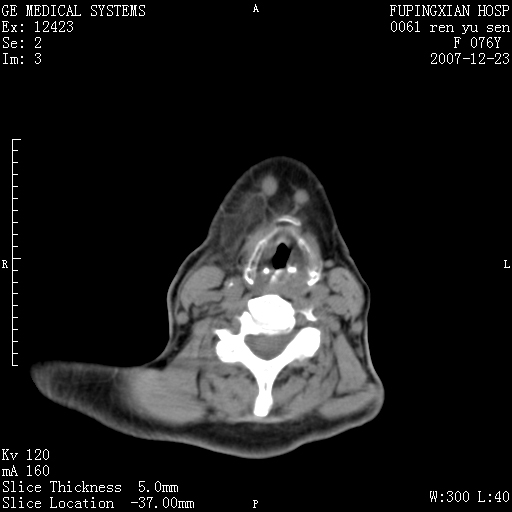

男性 76岁 下颌右侧磨牙区肿物数月, 约2.0*1.5cm大小波及颊舌侧,伴颌下淋巴结肿大。余(-)

右颈部颌下腺前可见一类圆形软组织密度影,密度不均,内见小片坏死区.颌下颈前可见两枚肿大淋巴结影.考虑淋巴结感染可能性大,建议增强扫描..

右侧第四磨牙缺失,局部牙槽骨质破坏,边界欠清晰,同侧颌下及竟不见多发肿大淋巴结显示。考虑肿瘤病变可能性大,感染待排